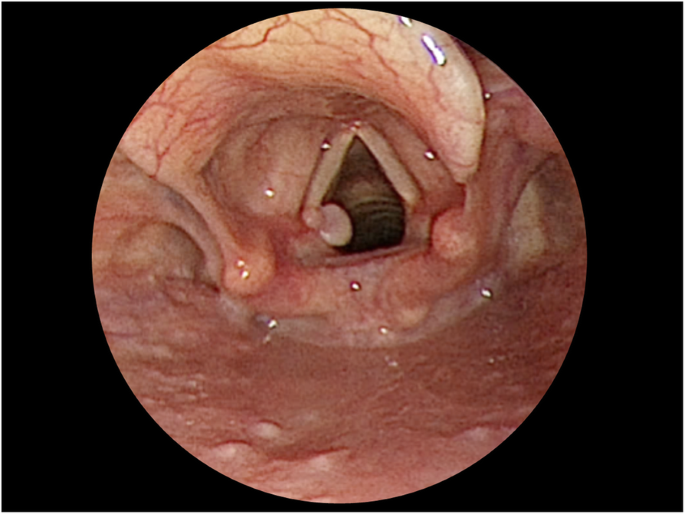

Her condition was unremarkable during the postoperative outpatient follow-ups at 1 week and 1 month. However, she developed hoarseness, forced voice, and voice fatigue two months after the surgery. Strobolaryngoscopy revealed symmetrical and movable vocal cords but also showed a granuloma over the left vocal process (Fig. 2A). She was prescribed oral prednisolone and a proton pump inhibitor along with voice therapy. Her symptoms improved thereafter, and the granuloma appeared to have shrunk significantly as seen on the 1-month follow-up strobolaryngoscopy (Fig. 2B).

Nevertheless, 2 months after the surgery, the patient started noticing hoarseness with voice fatigue. Strobolaryngoscopy revealed a contact granuloma over the posteromedial aspect of the left vocal cord (Fig. 3). She denied any voice abuse and had no history of gastroesophageal reflux disease. Although she was recommended conservative treatment with medication, she opted for granuloma excision. Her symptoms improved after the surgery.